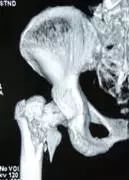

治愈百岁老人的髋部骨折——困难与挑战

无痛与微创

高龄老人髋部骨折传统的治疗方法是患肢制动或牵引,目前仅适用于内科疾病重、不能耐受麻醉和手术的患者及意识不清和不能自主活动的患者;存在治疗时间长、全身并发症多和病死率高等缺点。目前,为了让老人尽早恢复活动和自理能力,及时有效率的手术治疗已成为治疗老年髋部骨折的主要方法。

要减少老人手术带来的痛苦与风险,我们坚持采用先进的无痛和微创技术。手术损伤小,术后恢复快!

擅长:诊治各种慢性严重创伤疾病,老年骨质疏松骨折,关节软组织损伤及颈腰背痛等疾病。善于运用微创和显微手段及中西医结合治疗方法治疗新鲜和陈旧骨折骨关节严重损伤和运动损伤。